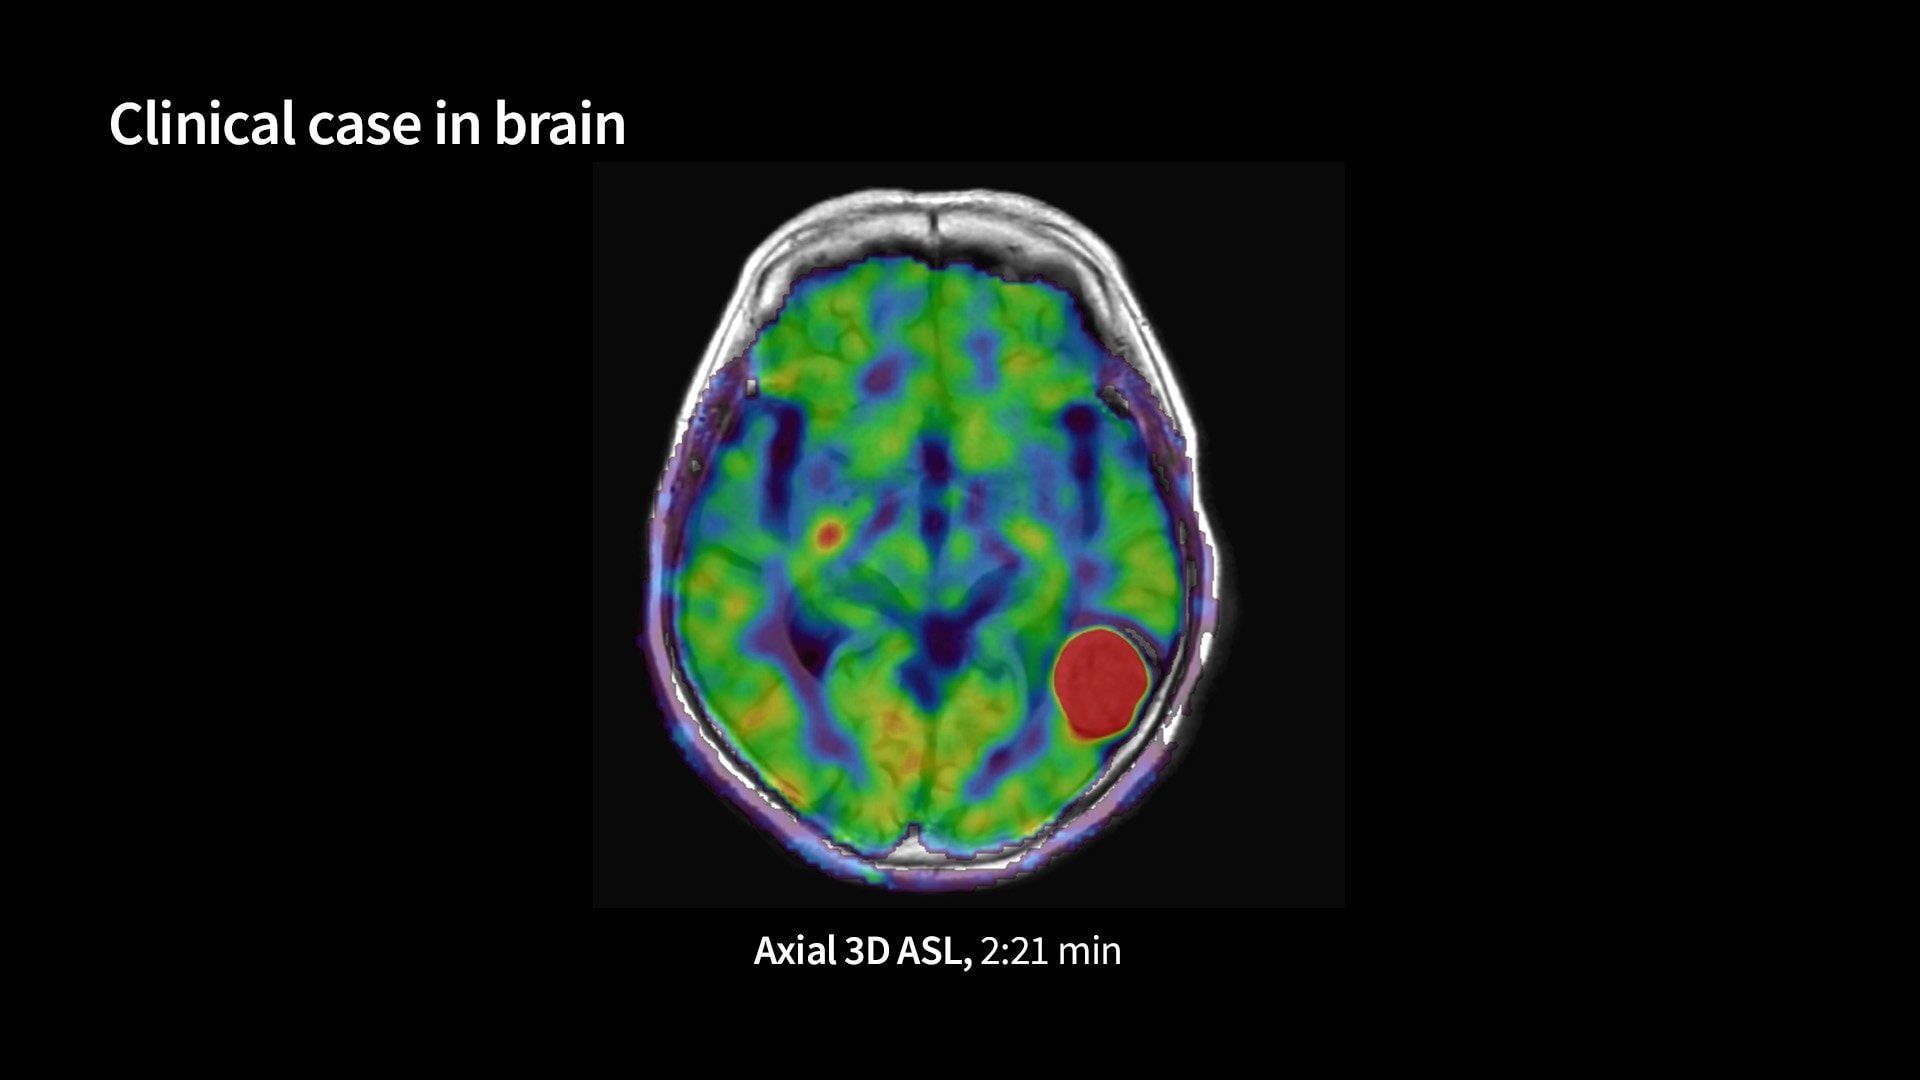

Quantifiable

Provides quantitative and actionable information